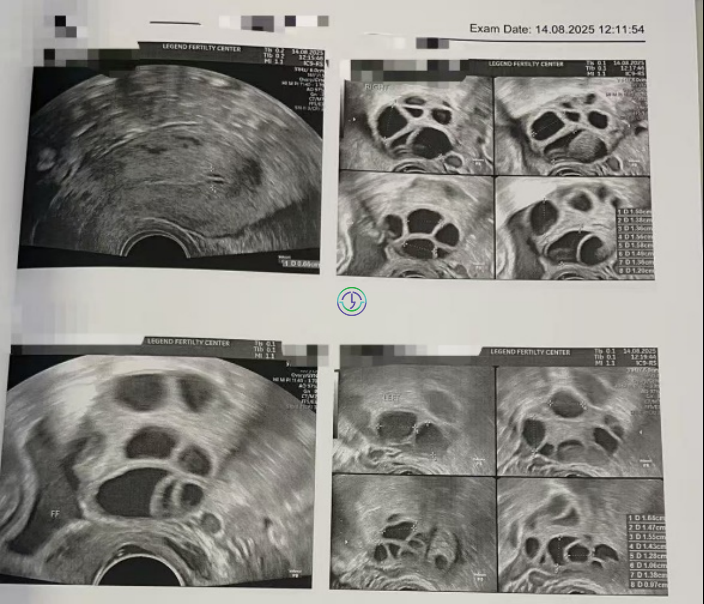

阴超检查:基础卵泡 20 颗左右

- 右侧卵泡 10 颗 (5-7mm)

- 左侧卵泡 10 颗 (5-7mm)

阴超检查:

- 右侧卵泡 11 颗 (12,10,10,8,8,8,8,7,6,6,6mm)

- 左侧卵泡 10 颗 (10,10,10,9,9,8,8,8,7,6mm)

促排第七天

- 右侧卵泡 12 颗 (17,17,15,14,12,12,10,10,10,10,10,10mm)

- 左侧卵泡 11 颗 (18,15,14,14,14,13,13,12,12,10,10mm)

促排第九天

- 右侧卵泡 11 颗 (20,18,17,16,15,15,13,13,12,11,10mm)

- 左侧卵泡 10 颗 (20,19,17,16,16,15,15,13,13,13mm)

EM子宫内膜厚度:9 mm